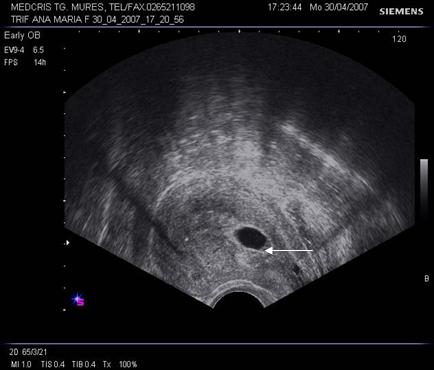

Fig nr. 69. Hematom

subchorial de dimensiune mare, langa orificiul cervical intern (cu sageata)

Fig nr. 70 Aceeasi sarcina ca in figura precedenta,la eco Doppler se observa lipsa fluxului sangvin in hematomul subchorial ( sageata)